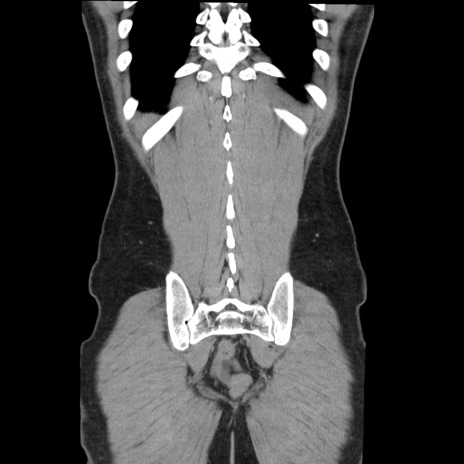

症例36(冠状断像)

【症例】20歳代 男性

【主訴】心窩部痛

【現病歴】今朝より上腹部痛あり。一旦軽快していたが再度出現したため救急要請。昨日夕に白身の魚を含む刺身を食べた。

【身体所見】BP 136/89mmHg、HR 74/min、BT 37.0℃、腹部:膨満、軟、心窩部に圧痛あり。反跳痛なし、筋性防御なし、腸雑音やや亢進あり。

【データ】WBC 17700、CRP 0.48